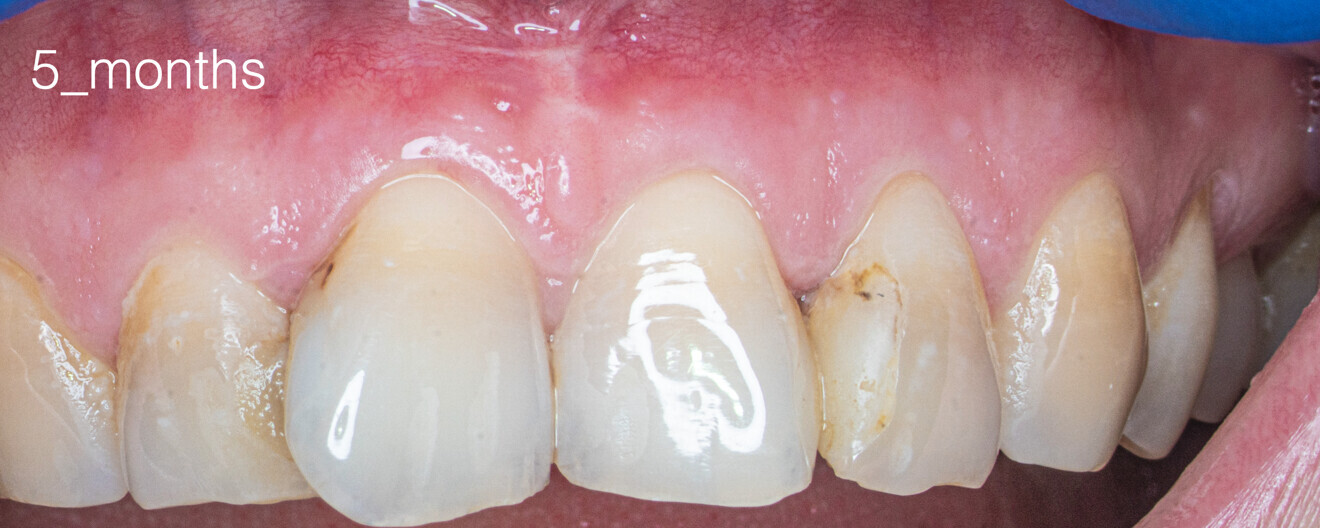

Fig. 15: Clinical situation after 14 days.

Recall appointments was performed after two (Figs. 16a & b) and four years (Figs. 17a & b). The radiographic examination showed the presence of bundle bone. The periodontal status was stable, and the tooth remained asymptomatic.